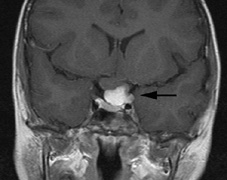

CNS hemangiomas are the most common tumor of VHL, affecting 60% to 80%, with a predilection for the cerebellum and spinal chord. An enlarging cystic component is a frequent finding in symptomatic tumors. Patients typically present in their early 30s; headaches or neck pain in affected individuals should not be ignored.172,173 On microscopy, CNS hemangiomas resemble retinal capillary hemangiomas. Their malignant potential is low.174 The treatment is surgical (Fig. 17, A and B).13

Fig. 17. Images from a 13-year-old boy with Von Hippel-Lindau syndrome. (a) Coronal postcontrast T1-weighted imaging reveals a cystic lesion with an enhancing nodule at the pial surface typical of a hemangioblastoma. (b) A second solid enhancing hemangioblastoma is seen at the craniocervial junction on a sagittal postcontrast T1-weighted image. (c) Associated cystic lesions (arrows) are seen within the pancreas.

Pancreatic lesions may be nonsecretory (most commonly cysts or cystadenomas) or secretory (islet cell tumor).179 In one study of 52 patients, 56% (29 patients) were found to have pancreatic lesions. The majority (19 of 29) had cystic changes only (Fig. 17C). Pancreatic lesions were the only abdominal manifestation of disease in 6 of 52 patients.180 In a separate study, pancreatic cysts did not show significant progression on follow-up examinations over an average period of 5 years.181 Like pancreatic cysts, islet cell tumors appear to be frequently asymptomatic.182